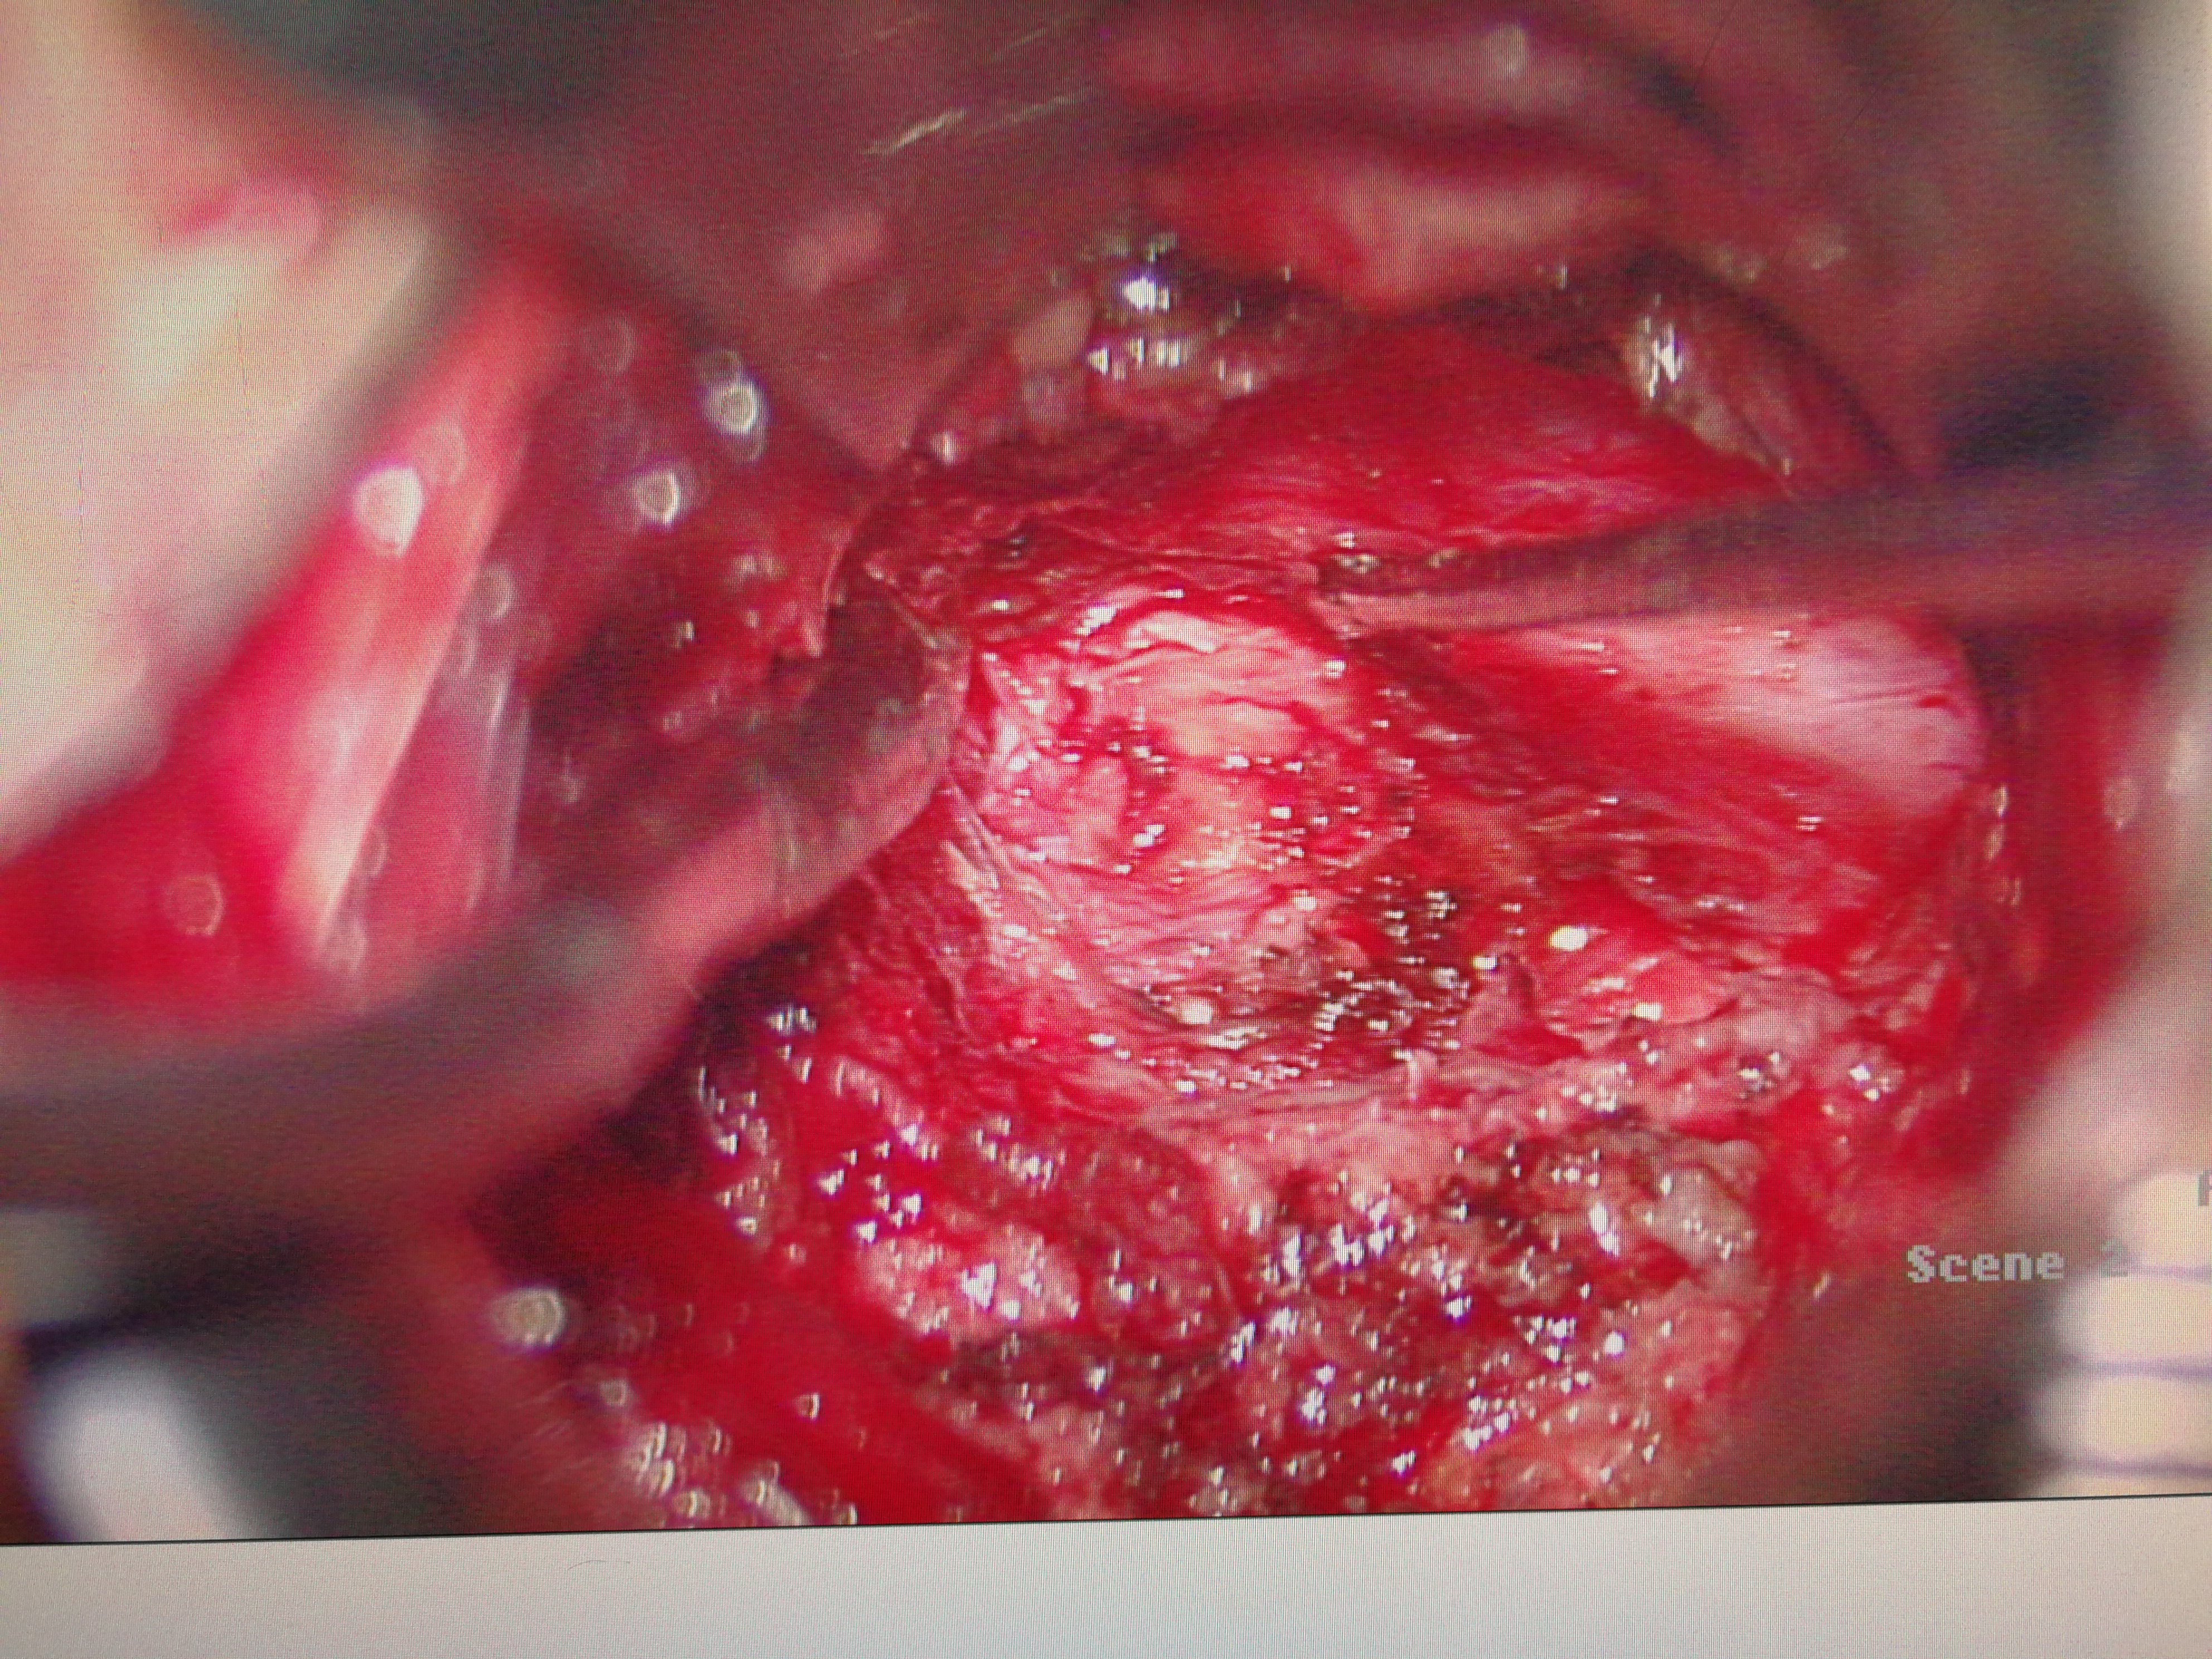

通道显微微创手术治疗腰椎间盘突出症

3968x2976 - 2828KB - JPEG